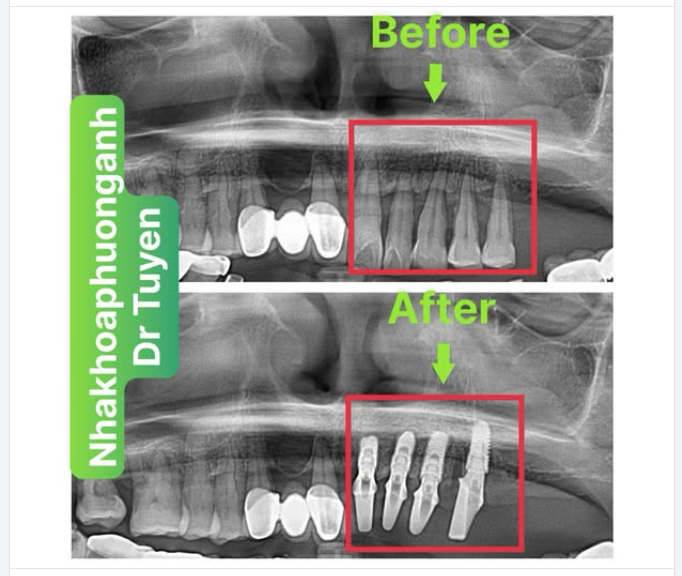

Trồng răng Implant khi bị tiêu xương hàm

Hàm trên của tôi bị tiêu xương nghiêm trọng và bác sĩ nói cần phải nhổ răng và dùng răng giả nguyên hàm. Tôi muốn trồng răng Implant nhưng với lượng xương bị tiêu thì điều này là không thể. Liệu việc sử dụng Emdogain (dẫn xuất từ khuôn men răng), các kĩ thuật tái tạo xương hay ghép xương có thể giúp bổ sung thêm lượng xương cần thiết để tiến hành trồng răng Implant không? Tôi không muốn phải dùng răng giả nguyên hàm.

Ghép xương ổ răng được thực hiện sau khi mất răng hoặc nhổ răng được gọi là sự bảo tồn ổ răng